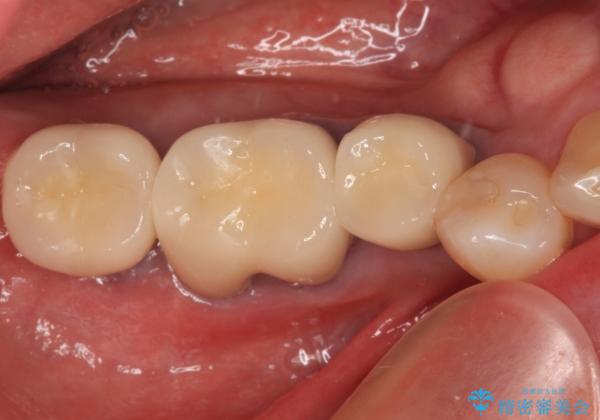

インプラント治療に当たり、手前の銀歯2本の審美回復も希望されたため、3歯のオールセラミッククラウンによる補綴治療を行うこととしました。

通常、奥歯を抜歯した状態で長年放置すると、咬み合う歯が伸びてきて、咬み合わせが乱れてしまうことが多いです。そのような場合には、部分的な矯正治療などが必要となるのですが、こちらの患者様は幸運なことに咬み合わせが乱れていなかったため、インプラント埋入から速やかに補綴治療を行うことができました。